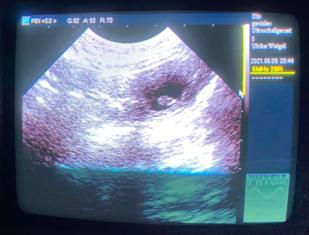

12.06.2021 - 24. Tag der Trächtigkeit

Der Ultraschall war so schön, Melli und ich konnten einige Lillis sehen :)

Herrlich!

Zählen unmöglich, ein normaler Wurf denke ich...

Das wird Überraschung bleiben!

Das Fotomachen war schwierig: Phoebe kraulen, schallen und knipsen war zu viel!

Immer wenn wir mal 3 gleichzeitig drauf hatten, war ein Atemzug später wieder alles weg ;)

Bin halt ein Laie, aber es geht ja auch nur darum zu wissen:

Juhuuu!!! Wir sind trächtig :) :)

Nun sind sie Realität, das ist sooo schön!